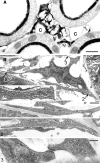

The renal interstitial compartment, situated between basement membranes of epithelia and vessels, contains two contiguous cellular networks. One network is formed by interstitial fibroblasts, the second one by dendritic cells. Both are in intimate contact with each other. Fibroblasts are interconnected by junctions and connected to basement membranes of vessels and tubules by focal adhesions. Fibroblasts constitute the "skeleton" of the kidney. In the renal cortex, fibroblasts produce erythropoietin and are distinguished from other interstitial cells by their prominent F-actin cytoskeleton, abundance of rough endoplasmic reticulum, and by ecto-5'-nucleotidase expression in their plasma membrane. The resident dendritic cells belong to the mononuclear phagocyte system and fulfil a sentinel function. They are characterized by their expression of MHC class II and CD11c. The central situation of fibroblasts suggests that signals from tubules, vessels, and inflammatory cells converge in fibroblasts and elicit an integrated response. Following tubular damage and inflammatory signals fibroblasts proliferate, change to the myofibroblast phenotype and increase their collagen production, potentially resulting in renal fibrosis. The acquisition of a profibrotic phenotype by fibroblasts in renal diseases is generally considered a main causal event in the progression of chronic renal failure. However, it might also be seen as a repair process.